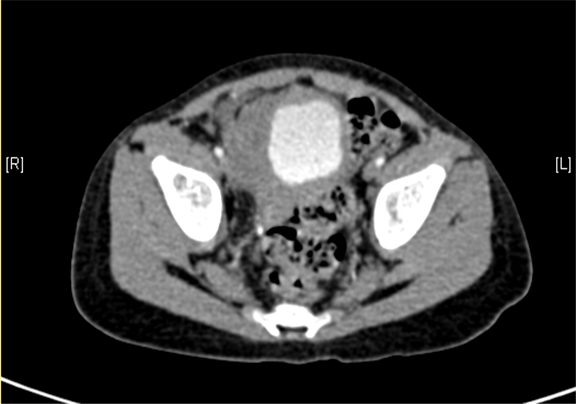

下腹部增强CT示右下腹腔内巨大软组织块影并右肾、输尿管积水。

术前CT检查:

动脉期

静脉期

平衡期